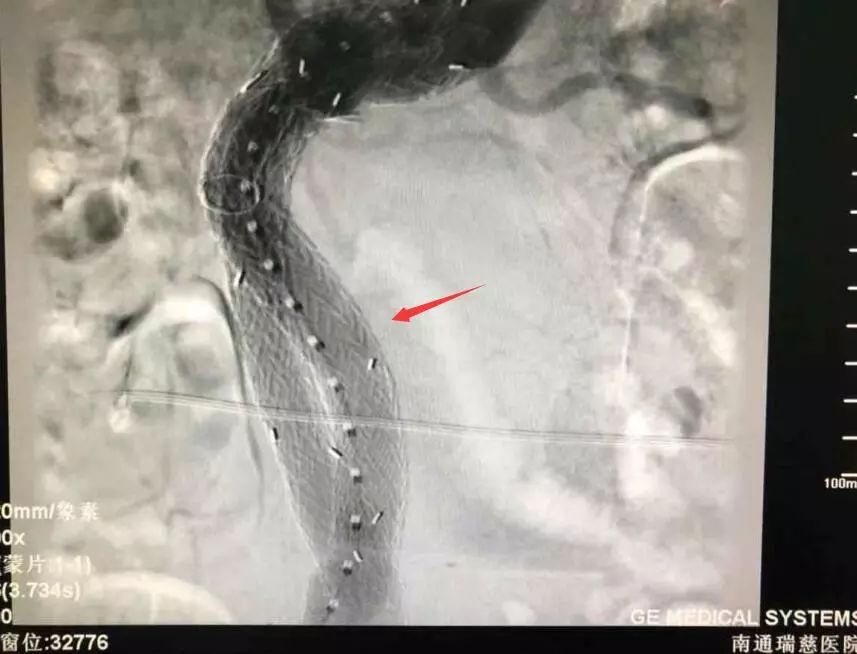

植入支架后動脈瘤顯影消失

回憶手術過程時,王主任說,老楊的手術相對來說確實難度較高,由于瘤體大,血液在里面形成渦流,導絲前進時容易彎折,無論是支架定位還是支架釋放,整個過程都十分考驗團隊的配合度。常規(guī)手術一般只用到兩個支架,老楊的瘤體較長,用上了四根支架才成功完全隔絕動脈瘤,杜絕內漏的發(fā)生,“就像是在患者的血管內建了一個立交橋,”王主任形容道。